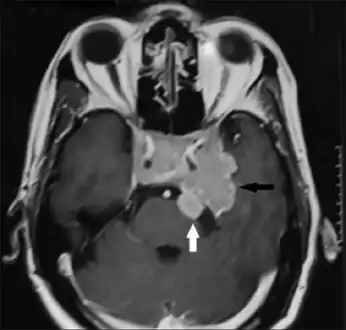

A doctor will test for prolactin blood levels in women with unexplained milk secretion (galactorrhea) or irregular menses or infertility, and in men with impaired sexual function and, in rare cases, milk secretion. If prolactin is high, a doctor will test thyroid function and ask first about other conditions and medications known to raise prolactin secretion. The doctor will also request a magnetic resonance imaging (MRI), which is the most sensitive test for detecting pituitary tumors and determining their size. MRI scans may be repeated periodically to assess tumor progression and the effects of therapy. CT scan also gives an image of the pituitary, but it is less sensitive than the MRI.

In addition to assessing the size of the pituitary tumor, doctors also look for damage to surrounding tissues, and perform tests to assess whether production of other pituitary hormones is normal. Depending on the size of the tumor, the doctor may request an eye exam with measurement of visual fields.

Prolactinoma on MRI